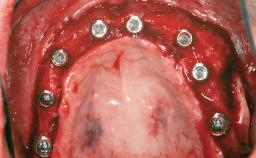

A 20-year-old woman was referred for implant therapy in 2004. Her medical history revealed no significant findings, and neither did she smoke nor take any medications. An extraoral examination revealed no abnormalities of the skin, hair or nails. The intraoral examination revealed only 11 permanent teeth clinically. These were normal in shape, size, and color. In addition, eight retained deciduous teeth (53, 62, 63, 71, 72, 73, 81, 82) were present. No abnormalities were detected during the general examination. The family history revealed that the patient’s father and two sisters were on record with similar conditions. The clinical examination revealed a thick gingival biotype. No recession of the attached gingiva was noted, but the retained deciduous teeth were mobile and unsightly. As a syndrome had not been diagnosed, the case was categorized as non-syndromic oligodontia.

# of Teeth 14

# of Implants 12

Type of Implants One-Piece|Reduced-Diameter

Attachment One-Piece|Reduced-Diameter